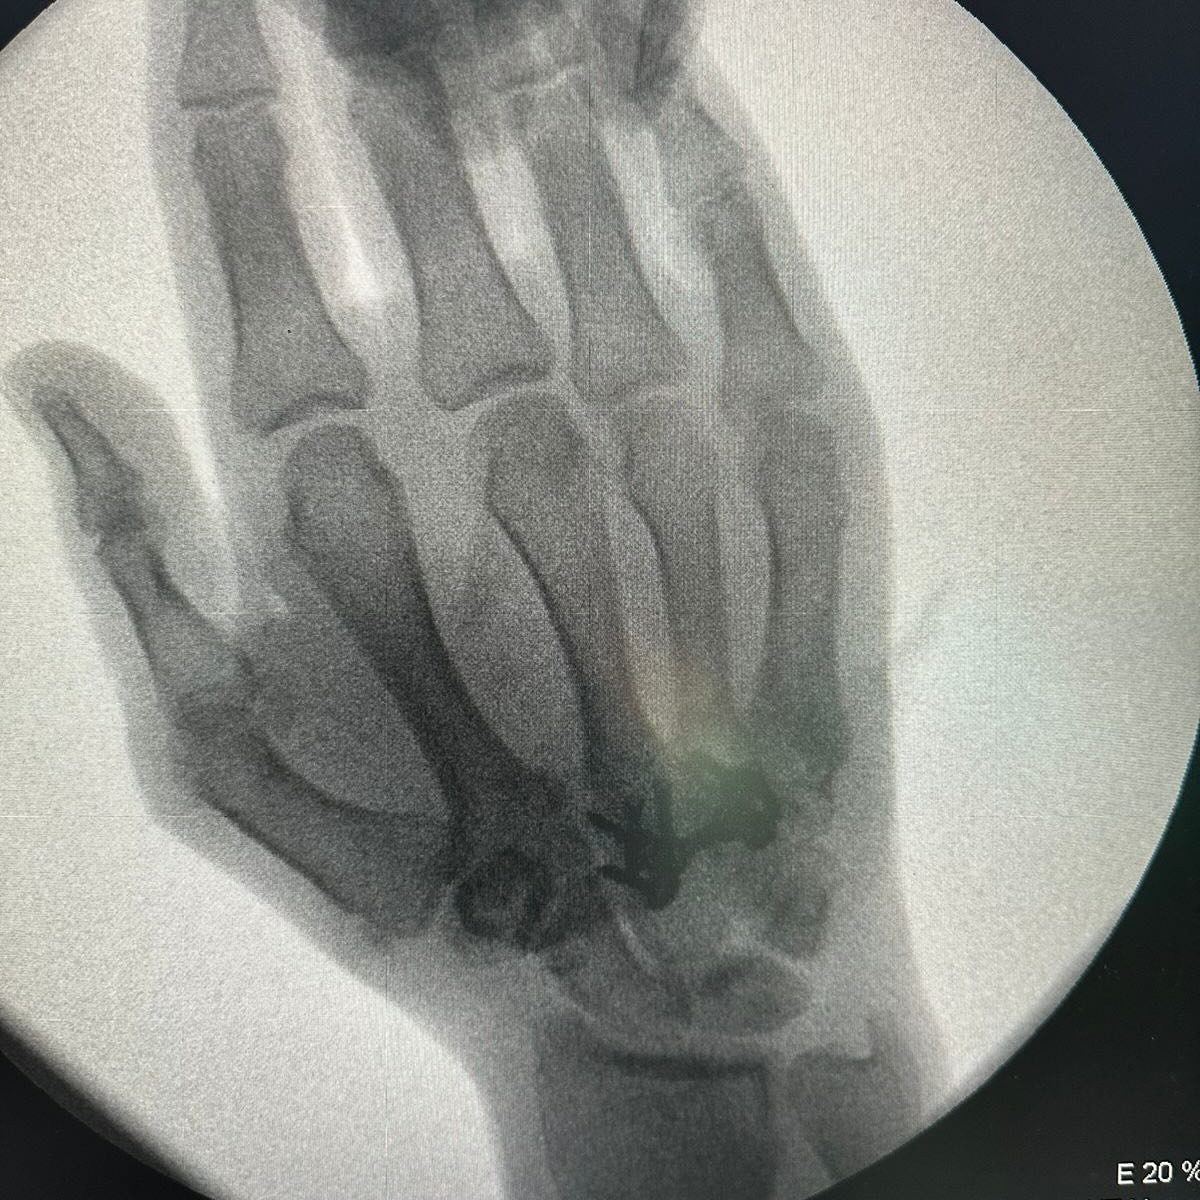

Rafael Ağayev: “Əlim üç dəfə qırılmışdı” FOTO VİDEO

5 qat dünya, 11 qat Avropa çempionu səhhətində yaranan problemlərdən danışıb. 40 yaşlı idmançı bildirib ki, hazırda vəziyyəti yaxşıdır: “Əlim üç dəfə qırılmışdı. Qolumda keyimə gedirdi. Ona görə də əməliyyat etdirdim. Xəstəxanadan çıxmışam, hazırda müalicəmi evdə davam etdirirəm”.